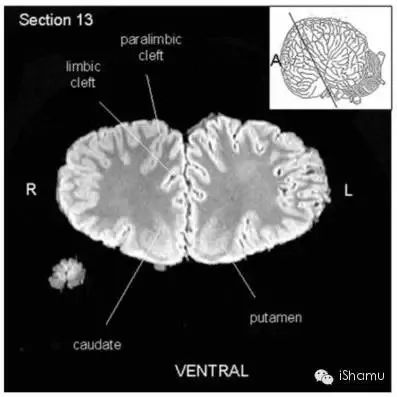

另外有一篇文献:“Neuroanatomy of the Killer Whale (Orcinus orca) From Magnetic Resonance Images”, 由神经生物学家Lori Marino et. al.于2004发表。该研究小组利用核磁共振成像技术,获得了宝贵的虎鲸脑部结构的图片。截了几张figure举几个栗子:

(Lori Marino et. al., 2004)

有医学背景的侠客朋友也应该看出来了。虎鲸的脑部解剖结构和人类脑部结构惊人的相似。同样有着高度折叠的大脑皮层沟回,有着形态和位置上高度相似的脑区(例如皮层,小脑,脑干,基底神经节),而且他们控制认知和情感的重要脑区Frontal lobe和Basal Ganglia也非常发达,同时也有着相对发达的参与记忆形成和学习的Limbic system包括著名的海马区,并且有着发达的Thalamus(丘脑)。